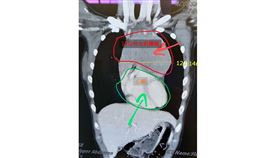

未爆彈!6.5cm「主動脈瘤」隨時索命

花蓮一名50多歲廖先生中風多年,去年因急性A型主動脈...